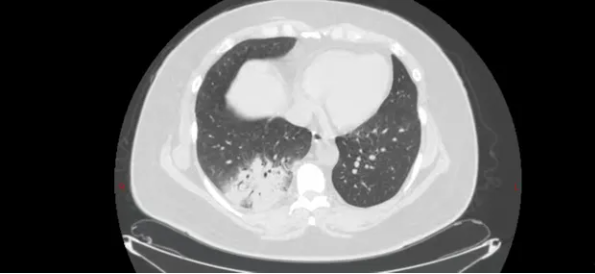

51岁的王女士(化名)持续发热5天,体温最高达39.5℃,伴全身乏力、关节肌肉酸痛。在外院输液治疗3天后仍反复发热,遂转至宝鸡市人民医院呼吸与危重症医学一科住院。主治医师李旭东接诊后,发现其胸部CT及血常规等检验结果提示非典型病原菌感染,结合患者家中养有鹦鹉的情况,高度怀疑鹦鹉热衣原体肺炎。学术主任王惠霞、科主任魏胜全与副主任医师贾汝臻综合患者长期养鹦鹉的爱好、病史、查体、CT片及相关检验结果,确认临床判断。